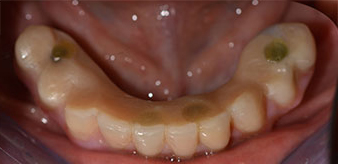

A three-dimensional cone beam computed tomography scan (CBCT, Planmeca) was performed to aid planning and minimize risks. This revealed that the quality and quantity of the available bone were sufficient for the surgery and immediate restoration using the Fast & Fixed method. Following the protocol for this concept, the implants are inserted at 35, 32, 42 and 45. Angling the distal implants by up to 45° shifts the emergence profile to posterior and generates a larger support polygon (Fig. 3).

Fast & Fixed method

Fig. 3